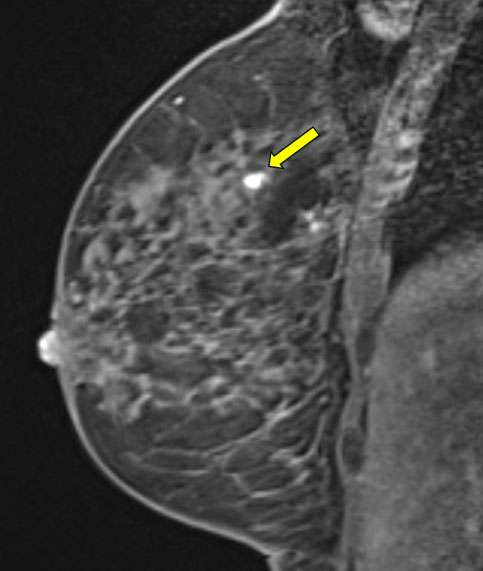

- Identify the biopsy site and determine lesion location using the grid localizer and depth within the breast from the grid (fig 2). Depending on institution, biopsy targeting software and/or post-processed images (such as subtracted images or reformatted images) may be used.

Figure 2. Sagittal T1-weighted fat saturated post contrast images demonstrate the biopsy target, a focus of enhancement.